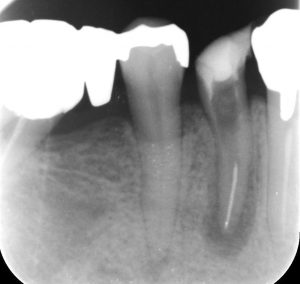

顕微鏡を用いしっかりと見える環境下にて、健康な歯を削らないようメタルコアを切削除去しました。

残っている白い筋が折れ込んだ金属・ファイルです。

ただ、今回のケースではだいぶ前から根管に取り残された金属片に感染源が付着している可能性があり、また、長く根管内に金属片が食い込み根管が塞がれている状況であったため、歯根の先端まで可及的に感染源を除去することができるよう金属片の除去を試みました。

下の写真は顕微鏡下で食い込んでいた金属片を除去したところです。

レントゲンでは歯根の先で歯が割れている像にも見えるのですがファイルを除去後、顕微鏡下で歯根内が割れていないことを確認し(漏洩もなし)、幸いにも膿瘍や感染による症状を消退させることができました。